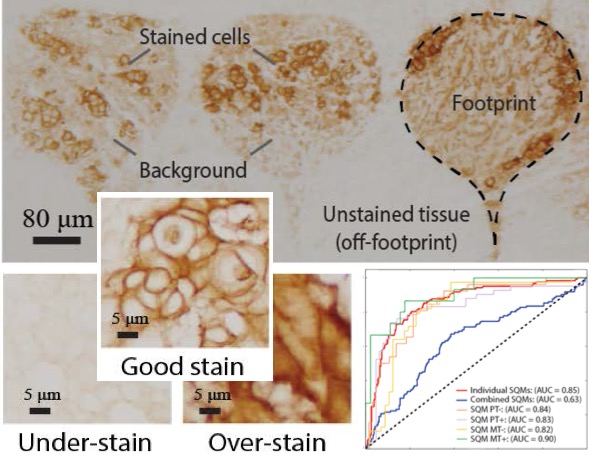

[2019] Nuri Murat Arar, Pushpak Pati, Aditya Kashyap, Anna Fomitcheva Khartchenko, Orcun Goksel, Govind V. Kaigala, and Maria Gabrani:

"High-Quality Immunohistochemical Stains through Computational Assay Parameter Optimization",

IEEE Trans Biomedical Engineering 66(10):2952-63, Feb 2019.

[2019] Nuri Murat Arar, Pushpak Pati, Aditya Kashyap, Anna Fomitcheva Khartchenko, Orcun Goksel, Govind V. Kaigala, and Maria Gabrani:

"High-Quality Immunohistochemical Stains through Computational Assay Parameter Optimization",

IEEE Trans Biomedical Engineering 66(10):2952-63, Feb 2019.

@article{Arar_high_19,

author = {Nuri Murat Arar and Pushpak Pati and Aditya Kashyap and Anna Fomitcheva Khartchenko and Orcun Goksel and Govind V. Kaigala and Maria Gabrani},

title = {High-Quality Immunohistochemical Stains through Computational Assay Parameter Optimization},

journal = {IEEE Trans Biomedical Engineering},

year = {2019},

volume = {66},

number = {10},

pages = {2952-63},

doi = {10.1109/TBME.2019.2899156}

}